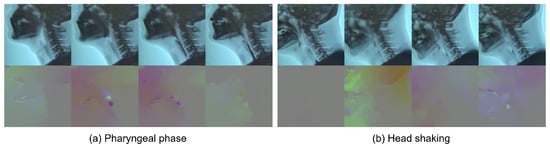

After the selection process, 3354 short clips of pharyngeal phase candidates were generated from 1085 long video sequences. Each video sequence had at least one pharyngeal phase occurrence. However, no candidates for pharyngeal phase intervals were generated in 88 out of 1085 video sequences. A total of 3354 short clips were labeled as being the pharyngeal phase (1674 samples) and others (1680 samples). As shown in Figure 4, RGB and optical flow visualization of the pharyngeal phase candidates shows the complexity of the optical flow analysis of subjects’ movements. The data for the video classification was divided into two sets, 2696 for training and 658 for validation.

Figure 4.

RGB (top) and optical flow (bottom) visualization of (a) positive sample—pharyngeal phase; and (b) negative sample—other action (e.g., head motions due to coughing).